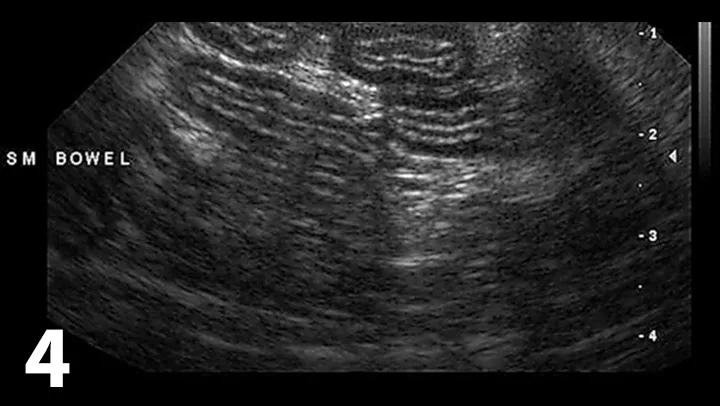

Figure 4

Ultrasound of the small intestine showing concurrent thickening of the muscularis propria layer and submucosal layer commonly seen in patients with IBD and small cell lymphoma.

• Abdominal ultrasound with careful evaluation of intestinal wall layering:

• Specific changes include thickening of the muscularis propria layer with or without concurrent thickening of the submucosal layer (Figure 4)

• Determine whether normal intestinal architecture is preserved because loss of layering is more consistent with intestinal lymphoma (large cell)20,21

• Evaluate regional lymph nodes carefully for size and echogenicity. Large hypoechoic lymph nodes are supportive of lymphoma